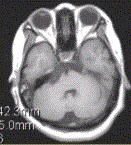

问题 患者女,41岁。右侧面肌抽搐。MRI显示如下图。 关于MRI,描述正确的是

选项 A.右侧桥前池可见T1WI等信号及T2WI高信号 B.未见异常 C.右侧三叉神经未见异常 D.右侧三叉神经可见包绕 E.基底动脉未见异常 F.基底动脉可见包绕

答案 ADF